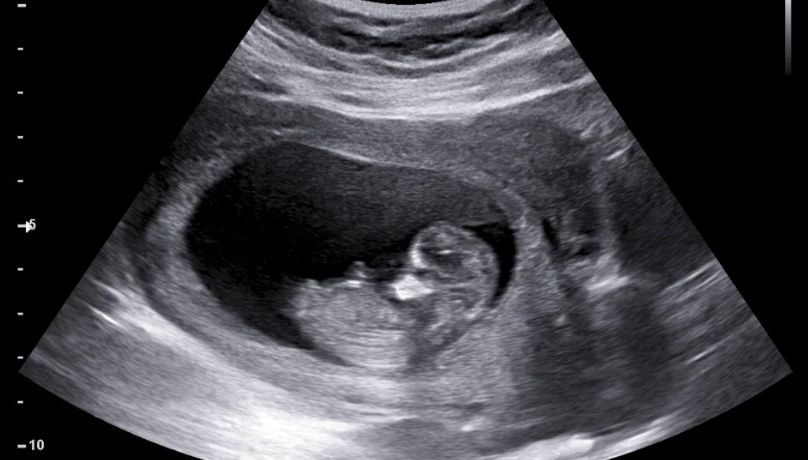

На ранних стадиях развития млекопитающих кластеры эмбриональных клеток определяют формирование жизненно важных органов — сердца, легких, печени и других. Это крайне важный процесс в исследованиях наук о жизни, и его лучшее понимание поможет в решении проблем врожденных заболеваний, таких как пороки сердца, и продвижении регенеративной медицины.

Чтобы раскрыть причины аномалий развития органов, команда под руководством профессора Юго-Восточного университета Линь Чэнци провела одноклеточный пространственный омиксный анализ эмбрионов мышей, отслеживая динамический процесс формирования органов.

Их работа выявила зону определения зачатков — критическую область, в которой во время эмбрионального развития появляются первые примитивные структуры развивающихся органов.

Уникальный сигнальный домен появляется в зоне определения зачатков на внутренне-внешней границе эмбриона, когда с момента зачатия проходит 7,75 дня.

Эта зона экспрессирует множество генов рецепторной сигнализации, создавая особую микроокружающую среду, способную интегрировать регуляторные сигналы из нескольких зародышевых листков, чтобы согласованно управлять развитием сердца и передней кишки.

Эти сигналы микроокружения впоследствии преобразуются в селективные программы экспрессии генов, которые инициируют формирование сердца и других зачатков органов.

«Открытие подтверждает, что нарушения микроокружения этой зоны, будь то генетические или средовые, в течение этой чувствительной фазы развития могут привести к анатомическим аномалиям органов», — резюмировала профессор университета Ло Чжоцюань.